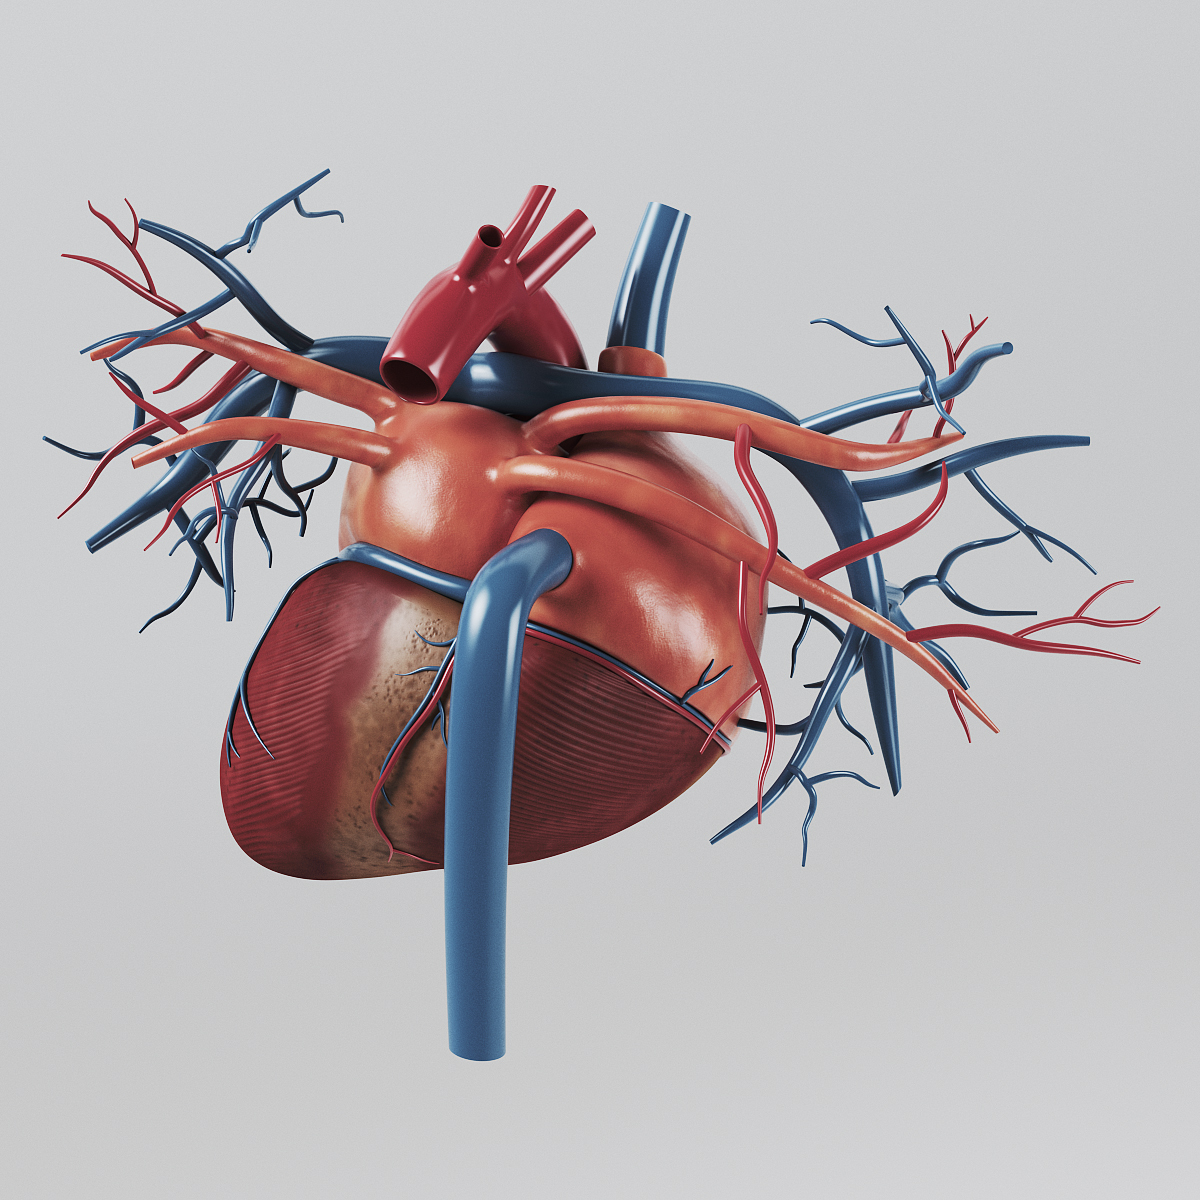

3d anatomy human heart  Show me a diagram of the human heart? Here are a bunch! - Interactive Biology, with Leslie Samuel

Human Heart Section 3D model | CGTrader  human heart - internal anatomy 3d model

human heart - internal anatomy 3d model  3D Illustration Human Heart 3D Images - Iwish Iwas

Human Heart Section 3D model | CGTrader  3d human heart

Human Heart Cutaway Anatomy 3D model section | CGTrader  Human Heart by Mutantenmaid on DeviantArt

human heart interior 3d model  Image of Human Heart 3D Illustration | Stock Image MXI28575

3d human heart section  human heart solidworks 3d model

human heart - internal anatomy 3d model  Heart Diagram Human Heart Images Hd 3D - img-Badr